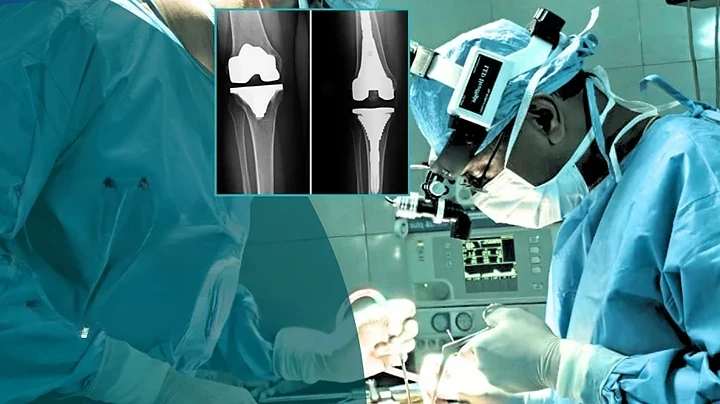

Primary Total Knee Replacement

2-Joint-Replacement-Surgery

Primary Total Hip Replacement

Robotic Knee Replacement Surgery

Revision Knee Replacement